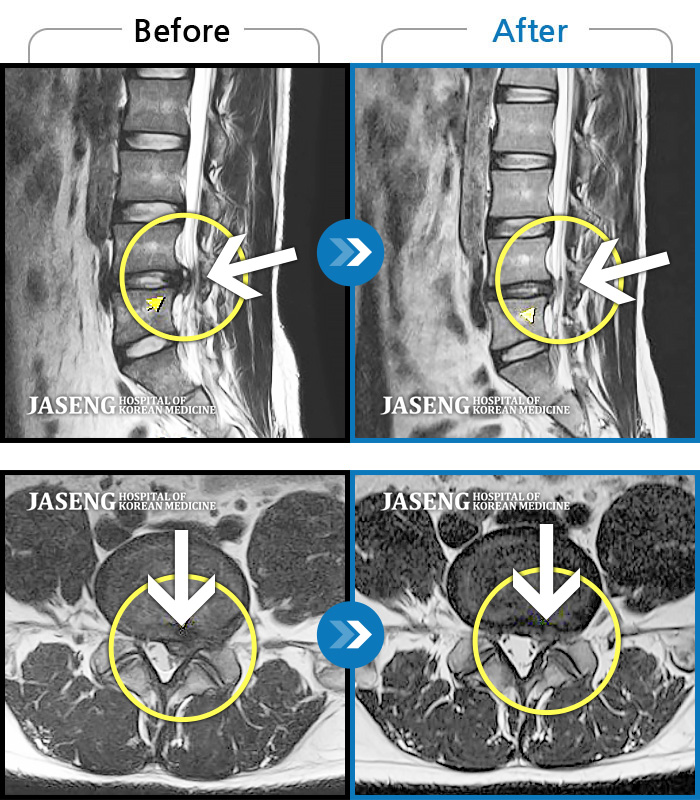

허리디스크

도움받은 사례

광주 · 이일석 원장

우측 허리 뻐근한 통증, 우측 허벅지부터 발목까지 이어지는 당김

촬영시기

2023.03.07 ~ 2023.12.23

2023.12.29